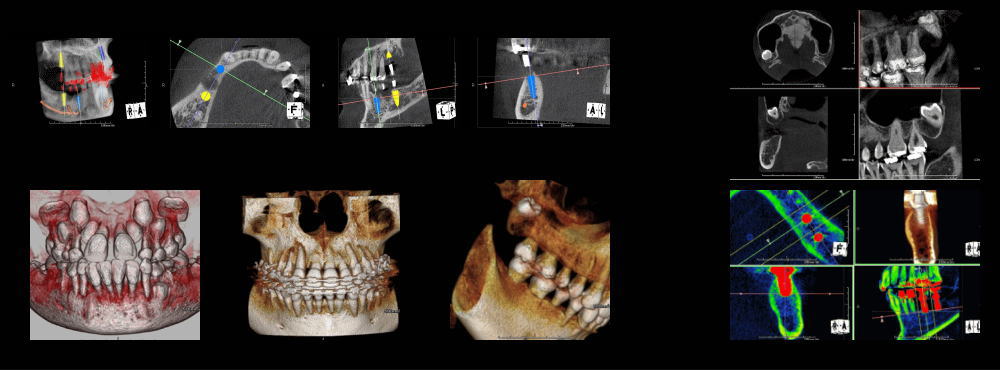

医科用CTに比べて、被爆線量が非常に少ないこと。(あるデータによると1/35という少なさです。)

CT撮影後即座に分析ができます。大幅な時間短縮ができました。